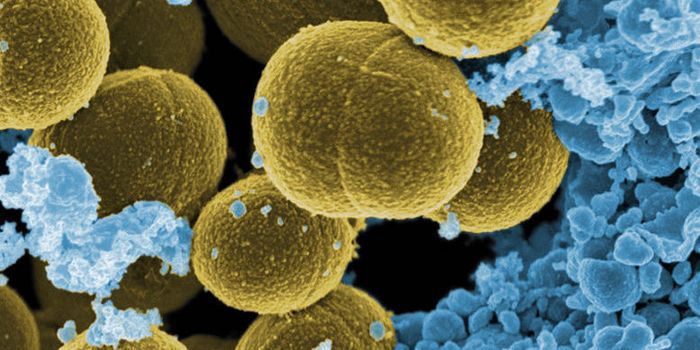

AUG 20, 2016Clinical & Molecular DXCan the staph superbug, also known as MRSA, be brought down by salt? Scientists finally expose a key weakness in these b ...